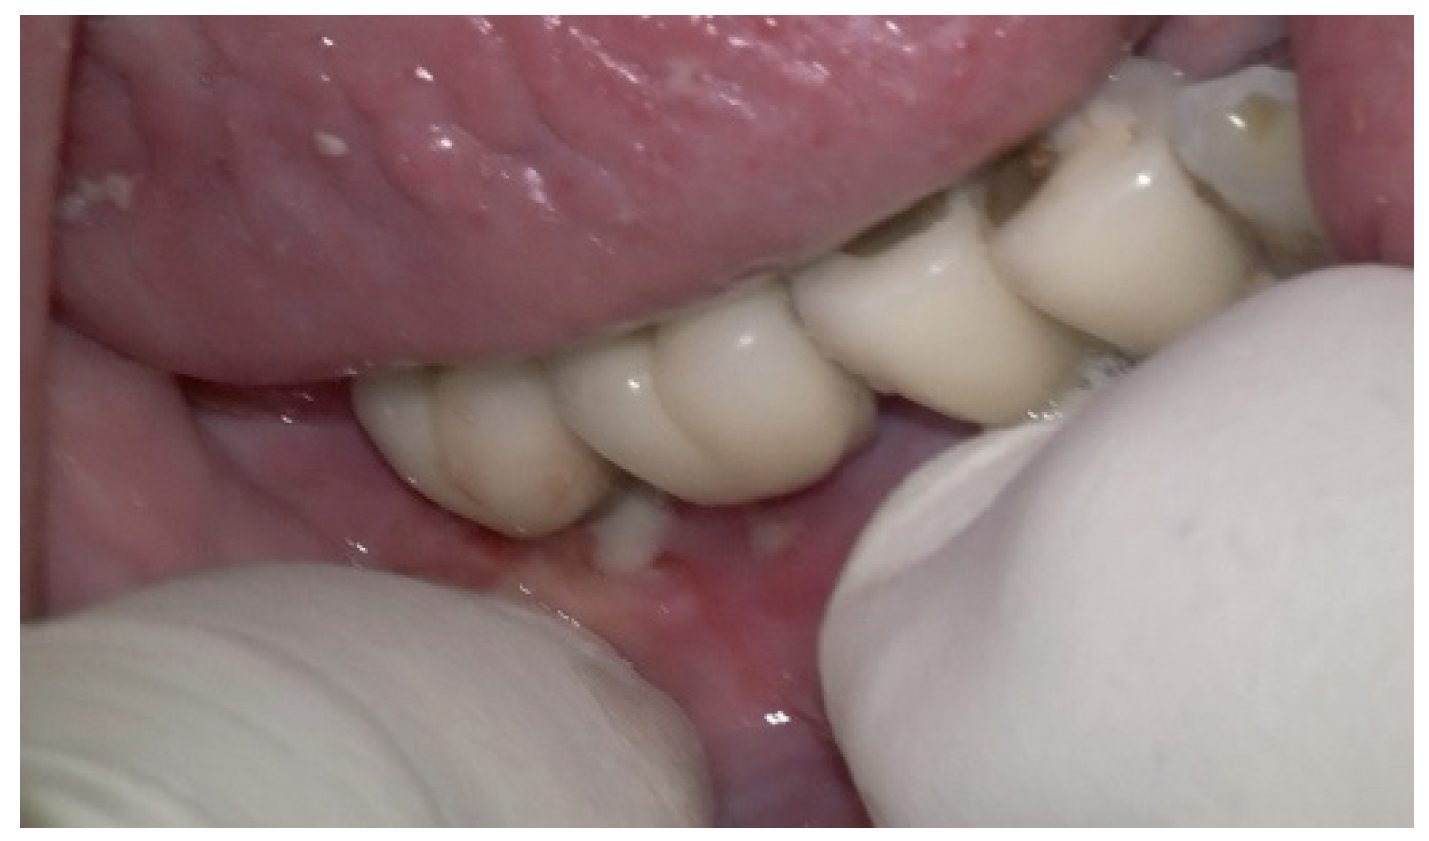

A generally healthy 63-year-old female presented to our clinic with chief complaints of foul odor and occasional pain emanating from dental implants located in the mandibular right quadrant (from implants #42 to #47). Clinical examination revealed peri-implantitis, with a high level of BoP and suppuration around the affected implants. The radiographic evaluation confirmed moderate-to-severe vertical bone loss, consistent with a diagnosis of peri-implantitis (Figure 19).

Before the surgical management following the Quadrant protocol, the fixed prosthesis was removed (Figure 20), and the region was cleaned. The surgical procedure involved a BSF, which was reflected lingually (Figure 21a,b) to facilitate access to the affected implant surfaces. With optimal access, thorough removal of granulation tissue occurred, minimizing the risk of lingual nerve damage and allowing for control of the flap.

The Quadrant protocol for peri-implantitis treatment was applied, as previously described. The dental implants #42–#47 received the insertion of the iMPACT to remove residual biofilm and contaminants directly from the implant surface, effectively renewing them without the need for implant retrieval. This step revitalized the implant surface, eliminating factors that contribute to peri-implantitis and establishing a stable foundation for healing (Figure 22a–c). The iMPACT’s cutting blades cut the implant surface and a portion of the bone (a controlled procedure). The granulation tissue, residual biofilm, and contaminants were meticulously removed with the tool, facilitating the restoration of implant surface integrity.

In this case, after achieving the renewed implant surface (machined), the regenerative procedure involving bone grafting and collagen membrane was not performed. The flaps were repositioned and secured with tension-free primary closure. The postoperative instructions included chlorhexidine 0.12% (Taro Pharmaceuticals, Haifa Bay, Israel) rinses and systemic antibiotic coverage for 5 days. Regular clinical and radiographic evaluations were conducted at 1 month, 3 months, 6 months, and 12 months, postoperatively. At the six-month follow-up, the clinical examination revealed significant improvements, with resolution of inflammation and no BoP; the patient reported a complete resolution of the initial chief complaints. Radiographs demonstrated stabilization and initial signs of bone regeneration around treated implants. At the 12-month follow-up, the bone level and PDs were stabilized (Figure 23), and the implant surface adequately accommodated the gingival tissue (Figure 24).

Figure 19. (a) Initial clinical assessment; (b) Periapical X-ray presenting the measurements (red arrows) from the platform to the bone; (c) The panoramic view shows the vertical bone loss found at baseline.